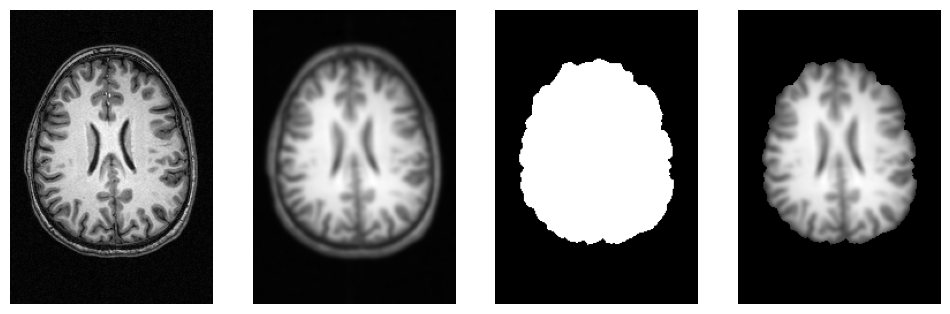

# Helper function to plot 3D NIfTI images

def plot_slice(fname):

# Load the image

img = nib.load(fname)

data = img.get_fdata()

# Cut in the middle of the brain

cut = int(data.shape[-1]/2) + 10

# Plot the data

plt.imshow(np.rot90(data[..., cut]), cmap="gray")

plt.gca().set_axis_off()

f = plt.figure(figsize=(12, 4))

for i, img in enumerate([input_file,

opj(wf_work_dir, "smoothflow/smooth/sub-01_T1w_smooth.nii.gz"),

opj(wf_work_dir, "smoothflow/skullstrip/sub-01_T1w_brain_mask.nii.gz"),

opj(wf_work_dir, "smoothflow/mask/sub-01_T1w_smooth_masked.nii.gz")]):

f.add_subplot(1, 4, i + 1)

plot_slice(img)